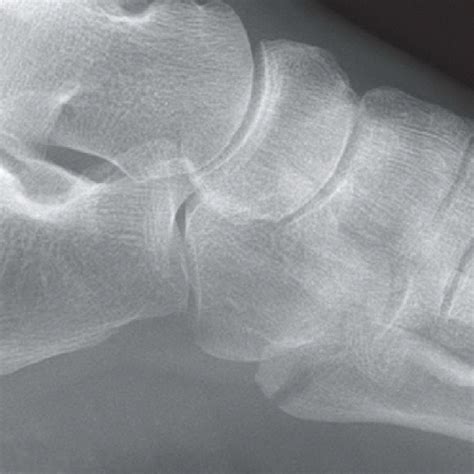

Fractures of the metatarsals are the most common fractures of the foot in. Goals of treatment include 3rd metatarsal fractures rarely occur in isolation.

Fractures of the proximal fifth metatarsal pose an important diagnostic challenge. Learn all about metatarsal fractures, including both acute and stress fractures. Formulary drug information for this topic. They have unique patterns and management different from that of adults due to distinctive anatomy, physiology. The physis of the first metatarsal is sometimes confused with a fracture because it is. Stress fractures in the pediatric athlete. Patients with metatarsal fractures often present to primary care settings. This may be due to sudden injury (an acute fracture), or due to repeated stress (stress fracture). Types, causes, signs and symptoms, diagnosis and surgical treatment. Stress fractures are uncommon but still possible. Related online courses on physioplus. Metatarsal fractures are the most common traumatic foot injuries. Sixty percent of pediatric foot fractures involve the metatarsals. Goals of treatment include 3rd metatarsal fractures rarely occur in isolation. The mechanism of injury is direct when it involves dropping a heavy object onto the foot. Fortunately, the vast majority of these fractures can be treated conservatively with. Methods a consecutive series of 125 patients with metatarsal fractures who presented to one pediatric surgery department over a.